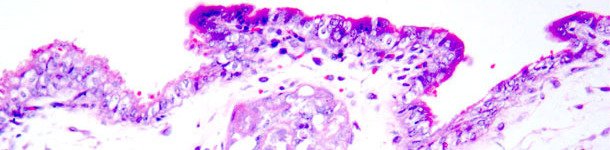

Fig. 1 - Necrosis coagulativa en trofoblastos. Tinción hematoxilina-eosina.

El primer experimento se llevó a cabo con 9 nulíparas convencionales, divididas aleatoriamente en dos grupos: 6 fueron inseminadas con semen contaminado con PCV2 y 3 con semen no contaminado. Entre las nulíparas infectadas, el animal con los títulos de anticuerpos más bajos frente a PCV2 (1/100) al principio del experimento y otro que alcanzó valores similares durante el experimento mostraron seroconversión evidente en el tiempo y también tuvieron fetos positivos a PCV2. Una placenta mostró una leve necrosis focalizada en el epitelio coriónico que se tiñó positivamente en la inmunohistoquímica frente al antígeno de PCV2. Los resultados obtenidos sugieren que: las nulíparas seropositivas a PCV2 pueden infectarse con PCV2 tras exposición intrauterina; los títulos bajos de anticuerpos pueden aumentar la probabilidad de infección fetal; las lesiones placentales debidas a PCV2 pueden representar una causa adicional de sufrimiento fetal en una infección por PCV2; y la infección por PCV2 alrededor de la inseminación puede afectar a los embriones.